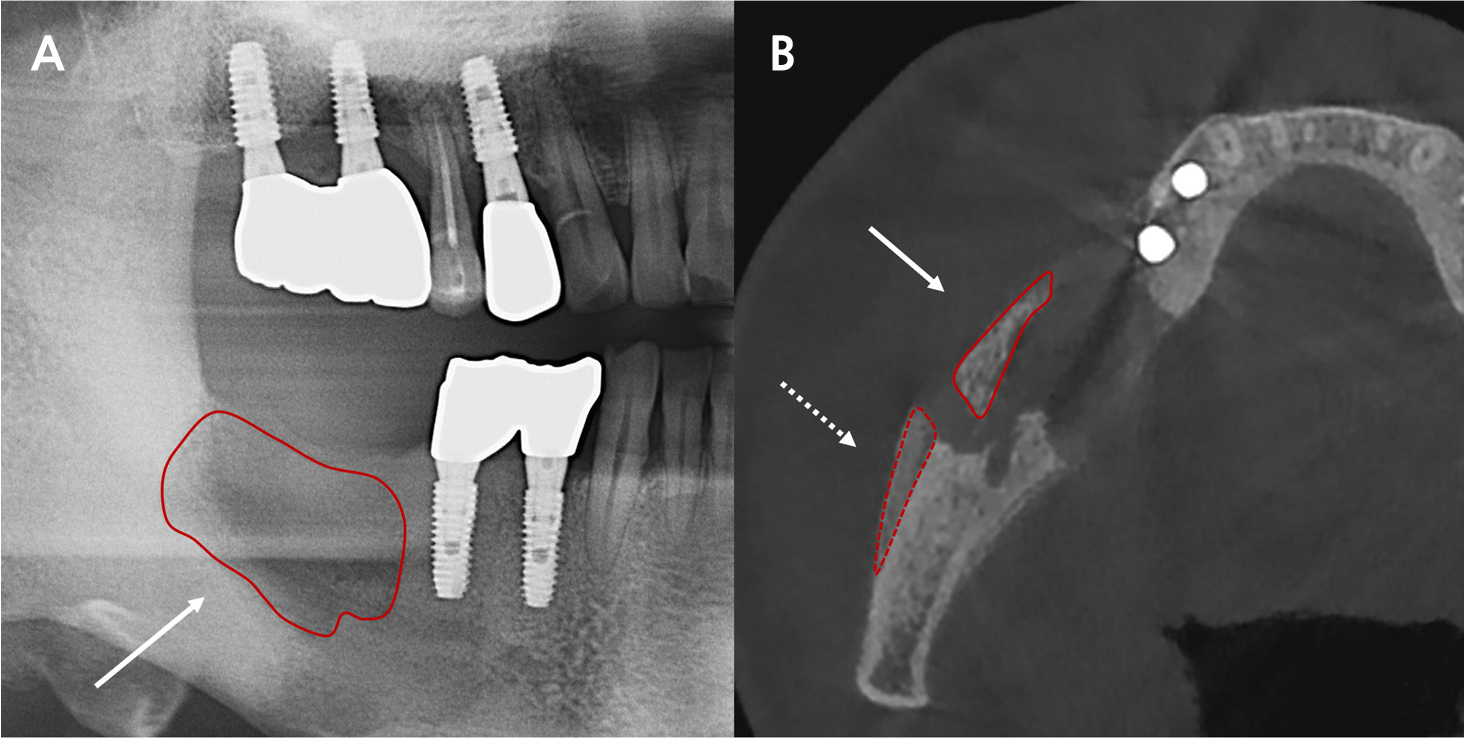

In 2016, dental implants were placed in Areas 47, 46, 45, and 44. In June, 2023, the patient experienced intermittent pain in these areas. Panoramic and other radiographic examinations revealed bone destruction around the implants (Fig. 1). In November 2023, implants i47 and 46 were removed at another institution.

Fig. 2

X-ray and a cone beam computed tomography (CBCT) image taken at the second visit. (A) Panoramic view. Compared to previous images, the implants were confirmed to have been removed, with more severe bone destruction (long arrow), (B) Axial view (CBCT). Cortical bone destruction and sequestrum (short arrow) with periosteal reaction (dotted arrow) in the surrounding area is noted.